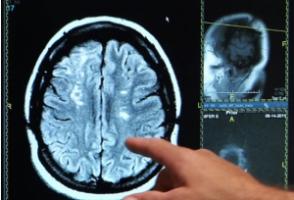

Maladie d'ALZHEIMER : Déclenchée par des facteurs épigénétiques ?

C’est la première fois que sont documentés des facteurs épigénétiques de la maladie d'Alzheimer. Cette équipe de l'Université de Pennsylvanie suggère ainsi, dans la revue Nature Genetics, que la maladie d'Alzheimer tardive peut-être déclenchée par des changements épigénétiques soit des changements dans l’expression des gènes sans modification de la séquence ADN. L'identification de ce processus épigénétique met en évidence de nouvelles stratégies de traitement possibles pour le traitement de la maladie à stade précoce.

L’équipe de la Perelman School of Medicine de la « Penn » a travaillé sur des tissus cérébraux post-mortem pour comparer des cellules cérébrales saines, jeunes et âgées, à des cellules atteintes de la maladie d'Alzheimer. Cette analyse apporte les preuves que les régulateurs épigénétiques désactivent certaines voies de protection cellulaire et activent en revanche des voies « pro-Alzheimer » chez les personnes atteintes de la maladie. Or, l'activité des régulateurs épigénétiques peut être inhibée par des médicaments, ce qui ouvre de nouvelles pistes thérapeutiques.